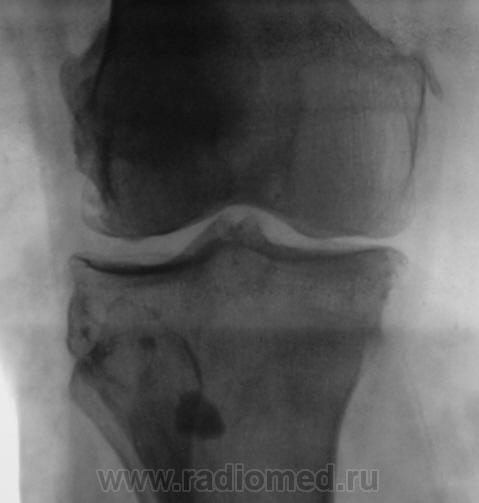

Пациентка направлена в рентгеновский кабинет на рентгенографию коленного сустава в диагнозом - "Артроз".

Валентин Львович, может это быть хондроматозом? И есть гонартроз+медиальный эпикондилит.

Да я не думаю, что это хондроматоз, пока сам в нерешительности, решил послушать мнения коллег.

Гонартроз 2 стадия.Обызвествление параартикулярных мягких тканей .Хондроматоз несколько по-другому выглядит и локализуется более скученно в слизистой сумке.Часто встечала в локтевом и плечевом суставах, в коленном ни разу не видела.

Если это системный процесс (метаб. кальциноз), то то же самое было бы и на снимках локт сустава? Крупное костное тело - сесамовидная кость либо  привет от Осгуд-Шлаттера. Насчет мелких - кроме цистицеркоза ничего в голову не приходит.